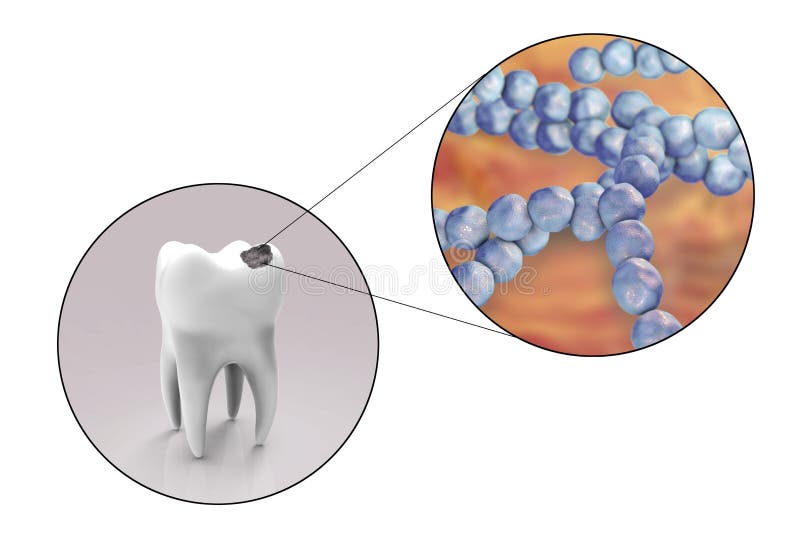

Dental Caries Clipart - Clipground

clipground.com

clipground.com

germs tooth caries clipart dental illustration stock sad cliparts clipground vector teeth attacked poor